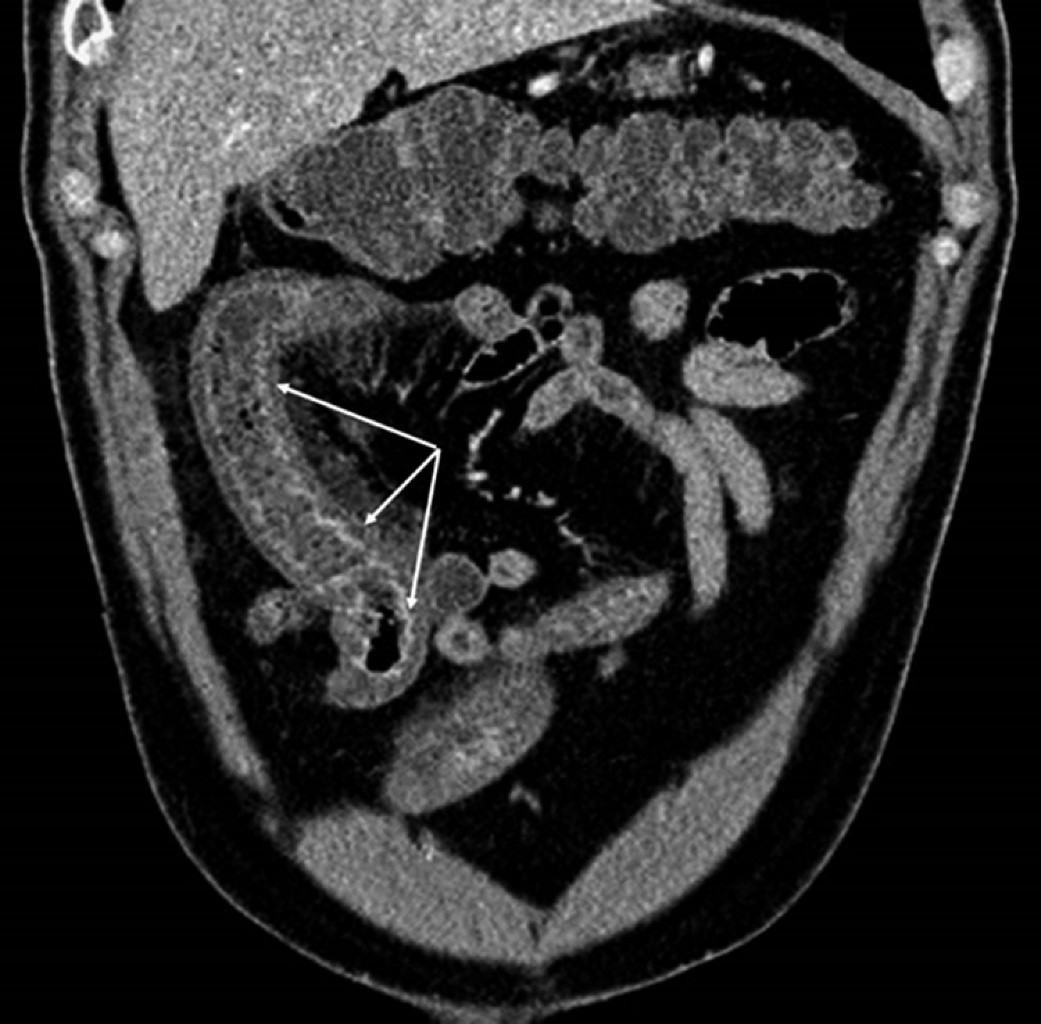

Introduction: polyarteritis nodosa (PAN) is a necrotizing vasculitis presenting as a multisystem disease. With aneurysmal formations in visceral arteries, especially in superior mesenteric artery branches. Case report: a 44-year-old male with abdominal pain in the epigastrium, nausea, and hematochezia, presenting petechiae on the trunk, abdomen, and pelvic limbs, predominantly with neutrophilic leukocytosis, negative immunological markers (ANCA). In abdominal angiotomography, sacculations are observed in superior ileal vessels. Conclusion: PAN is a rare multisystem vascular disease with a predilection for medium-caliber vessels. It is essential to identify radiological signs since a diagnostic delay leads to complications such as intestinal ischemia, aneurysmal ruptures, and others.

Figure 3